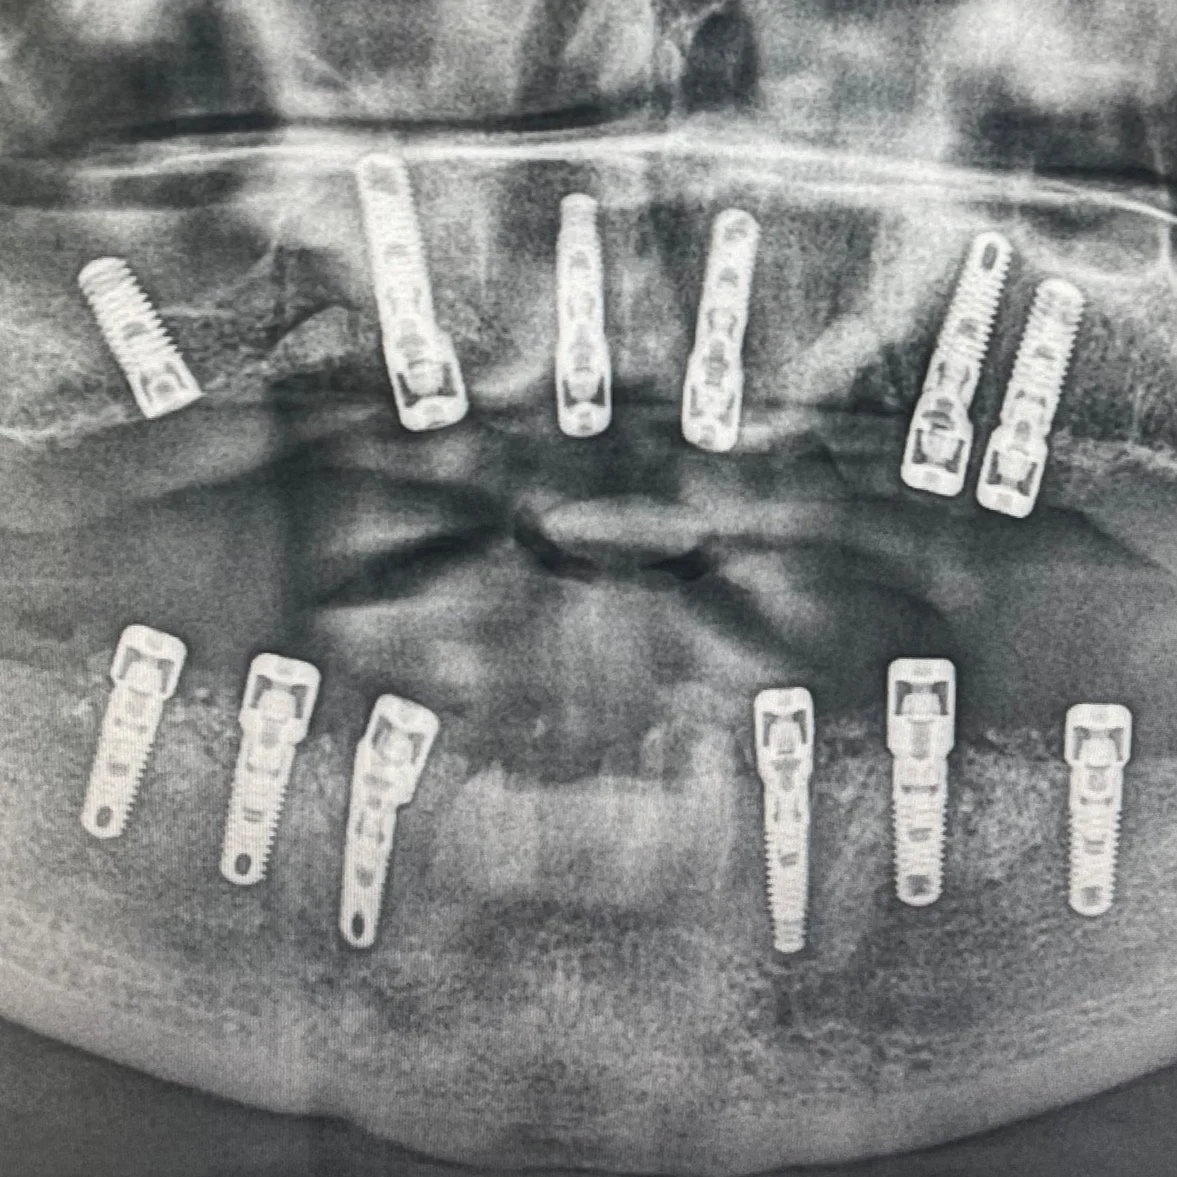

Dentalni snimak koji pokazuje implante ili implantate u obje vilice.

Hirurgija

Hirurškim procedurama se bezbolno vade neodrživi zubi i ugradnjom implantata se nadoknadjuju isti. Svrha hirurgije je očuvanje zdravlja i funkcionalnosti usne duplje uz maksimalnu sigurnost i udobnost naših pacijenata.